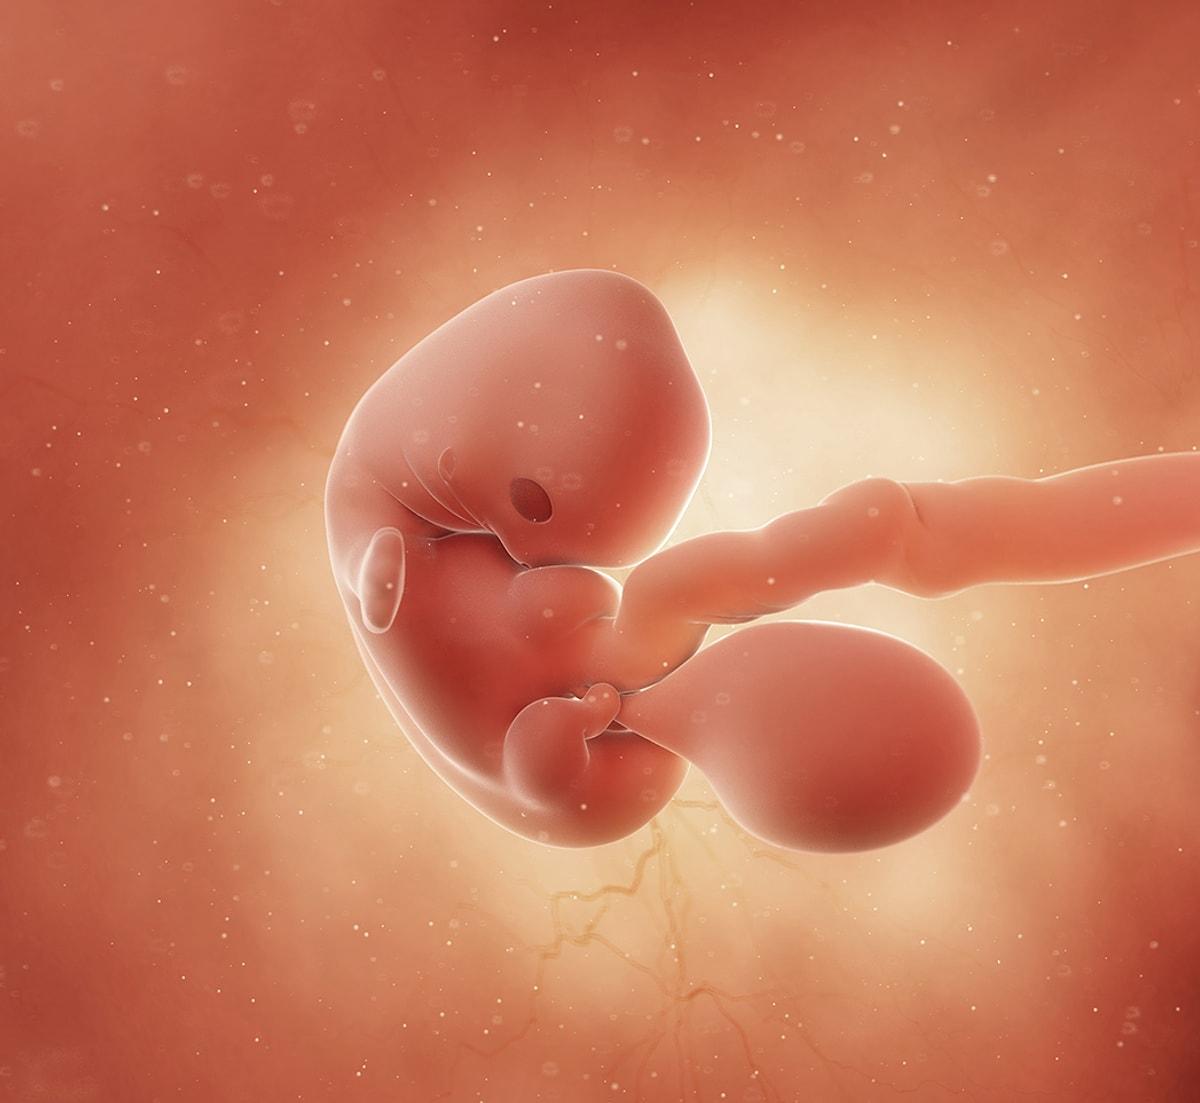

Развитие зародыша на 12 неделе: визуальный обзор

Раздел: Визуальные уроки